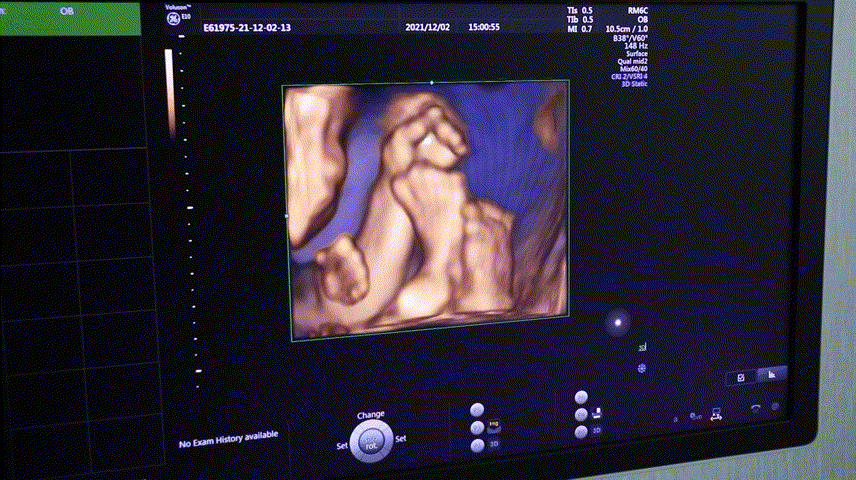

四维彩超是孕期排畸时十分常用的方式,检查宝宝的健康情况,排查出畸形的宝宝。

可以让孕妈和医生清楚真实的看到宝宝的发育情况,让孕妈第一时间见到自己宝宝的样子~

四维彩超的全称是四维彩色超声诊断仪,是彩色超声设备。

四维彩超能够表面成像,可以查看胎儿是否先天性体表畸形,如脑膜膨出,是否唇腭裂、脊柱裂等先天畸形,并为胎儿先天性心脏疾病提供准确的科学依据,及早发现及早地做出解决方案

我院引进VOLUSON S6设备,由20年以上临床经验医生操作,可以更加准确、快速地判断胎儿的状况,给予孕妈们专业的意见。